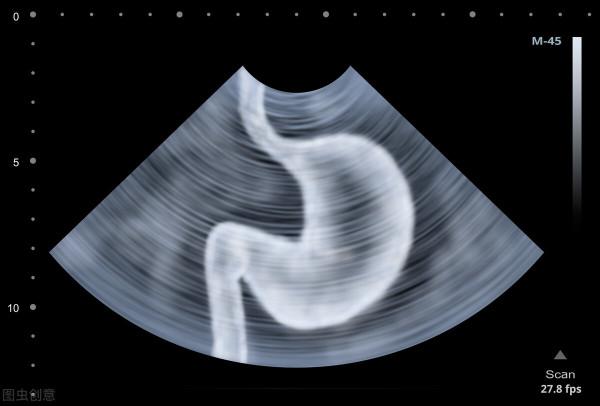

胃輕癱也稱為胃排空延遲,是糖尿病胃腸植物神經病變常見的症狀。糖尿病長期高血糖會損害神經,其中有一種神經叫做迷走神經,

在正常消化過程中,胃收縮以幫助分解食物並將其移入小腸,迷走神經主要控制食物透過胃的運動。當迷走神經受損時,胃和消化道其他部位的肌肉就不能正常運作,食物不能快速地透過消化系統,就會擾亂胃的收縮,妨礙消化,進而引起胃輕癱。